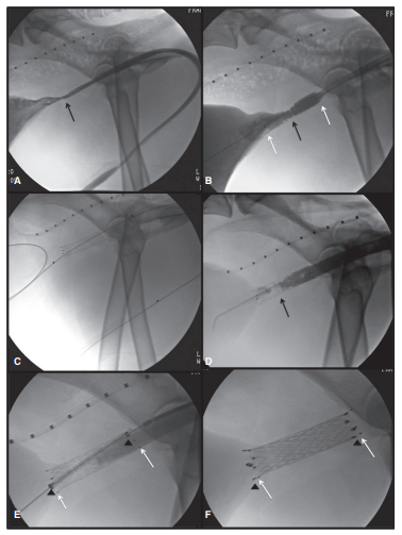

요도스텐트를 이용한 신속한 치료

요도스텐트 시술은 요도의 통로를 열어 소변 배출을 원활하게 도와줍니다. 이를 통해 요도폐색을 신속히 해결할 수 있으며, 불필요한 절개 없이 (비침습 시술) 안전하게 시술을 진행할 수 있습니다.

요도스텐트 삽입 시술 예시 사진